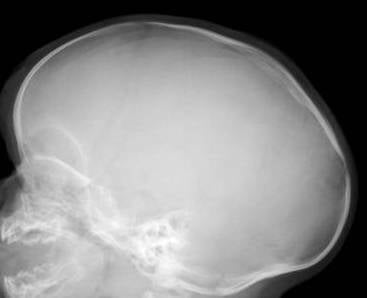

Allereerst de foto's van begin juni. Heel duidelijk kun je zien dat de zogenaamde pijlnaad gesloten is en de bootvorm van de schedel.

De volgende foto's zijn van de eerste controle na drie weken en 4 dagen. Hier kun je goed de veren zien zitten. Ik heb het contrast van de eerste foto iets vergroot zodat je duidelijk zaagsnedes kunt zien zitten en hoever deze al wijken door druk van de veren. Ook kun je al goed zien hoe de bootvorm is afgenomen aan de achterkant.